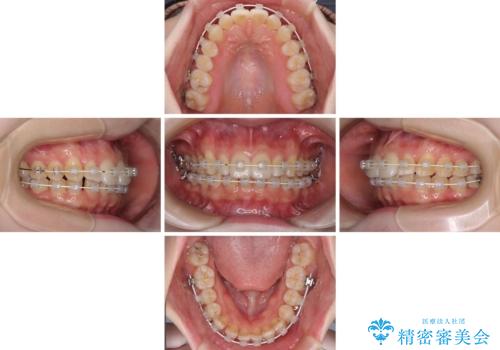

- 矯正装置

- 審美装置

- 治療期間

- 2年2ヶ月

半年もせずにインビザラインを全く使用することができなくなってしまったので、治療開始から1年ほどでワイヤー矯正へ変更することとなりました。

ワイヤー矯正へ変更してからはあっという間に治療が進み、1年弱で終えることができました。